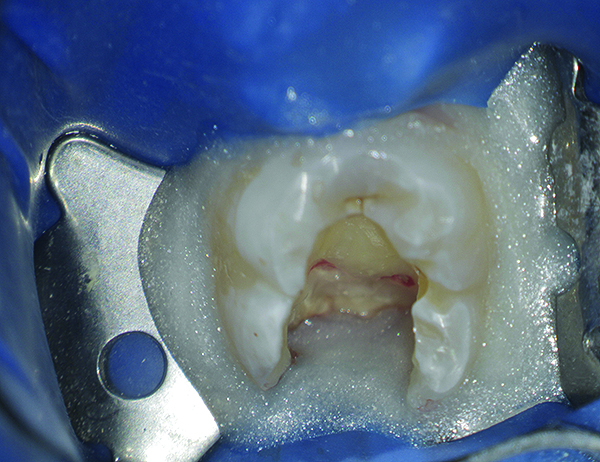

(4. AND 5.) This maxillary first molar was to have endodontic therapy following diagnosis of irreversible pulpitis.

Figure 4

(7.) This conservative size preparation was enough to explore and find the three main canal orifices to the root canals.

Figure 7

(9.) The MB2 canal orifice was then exposed and a file was used to reach working length.

Figure 9